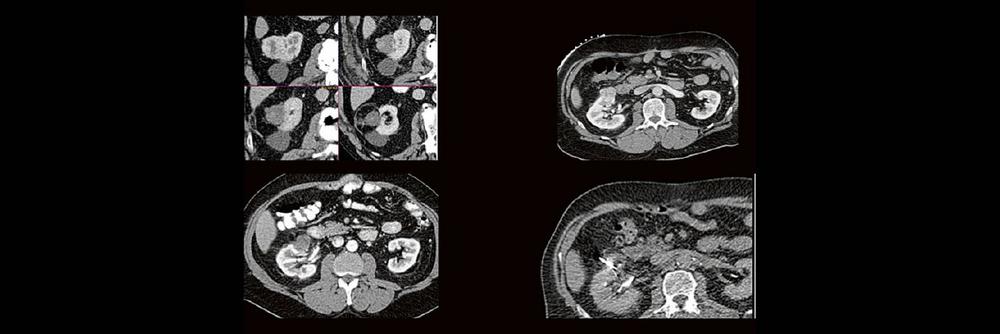

Alex Riemer Moderne CT-Scanner unterstützen die Anwenderinnen und Anwender bei der Durchführung der meisten CT-Untersuchungen. Hierzu zählt auch das automatische Erstellen von streng coronalen und sagittalen Multiplanaren Reformatierungen (MPR´s). Es gibt jedoch CT-Untersuchungen, bei denen die MPR´s individuell an die Anatomie angepasst werden müssen. Doch gerade bei diesen Bildnachverarbeitungen gibt es oft Unsicherheiten darüber, worauf